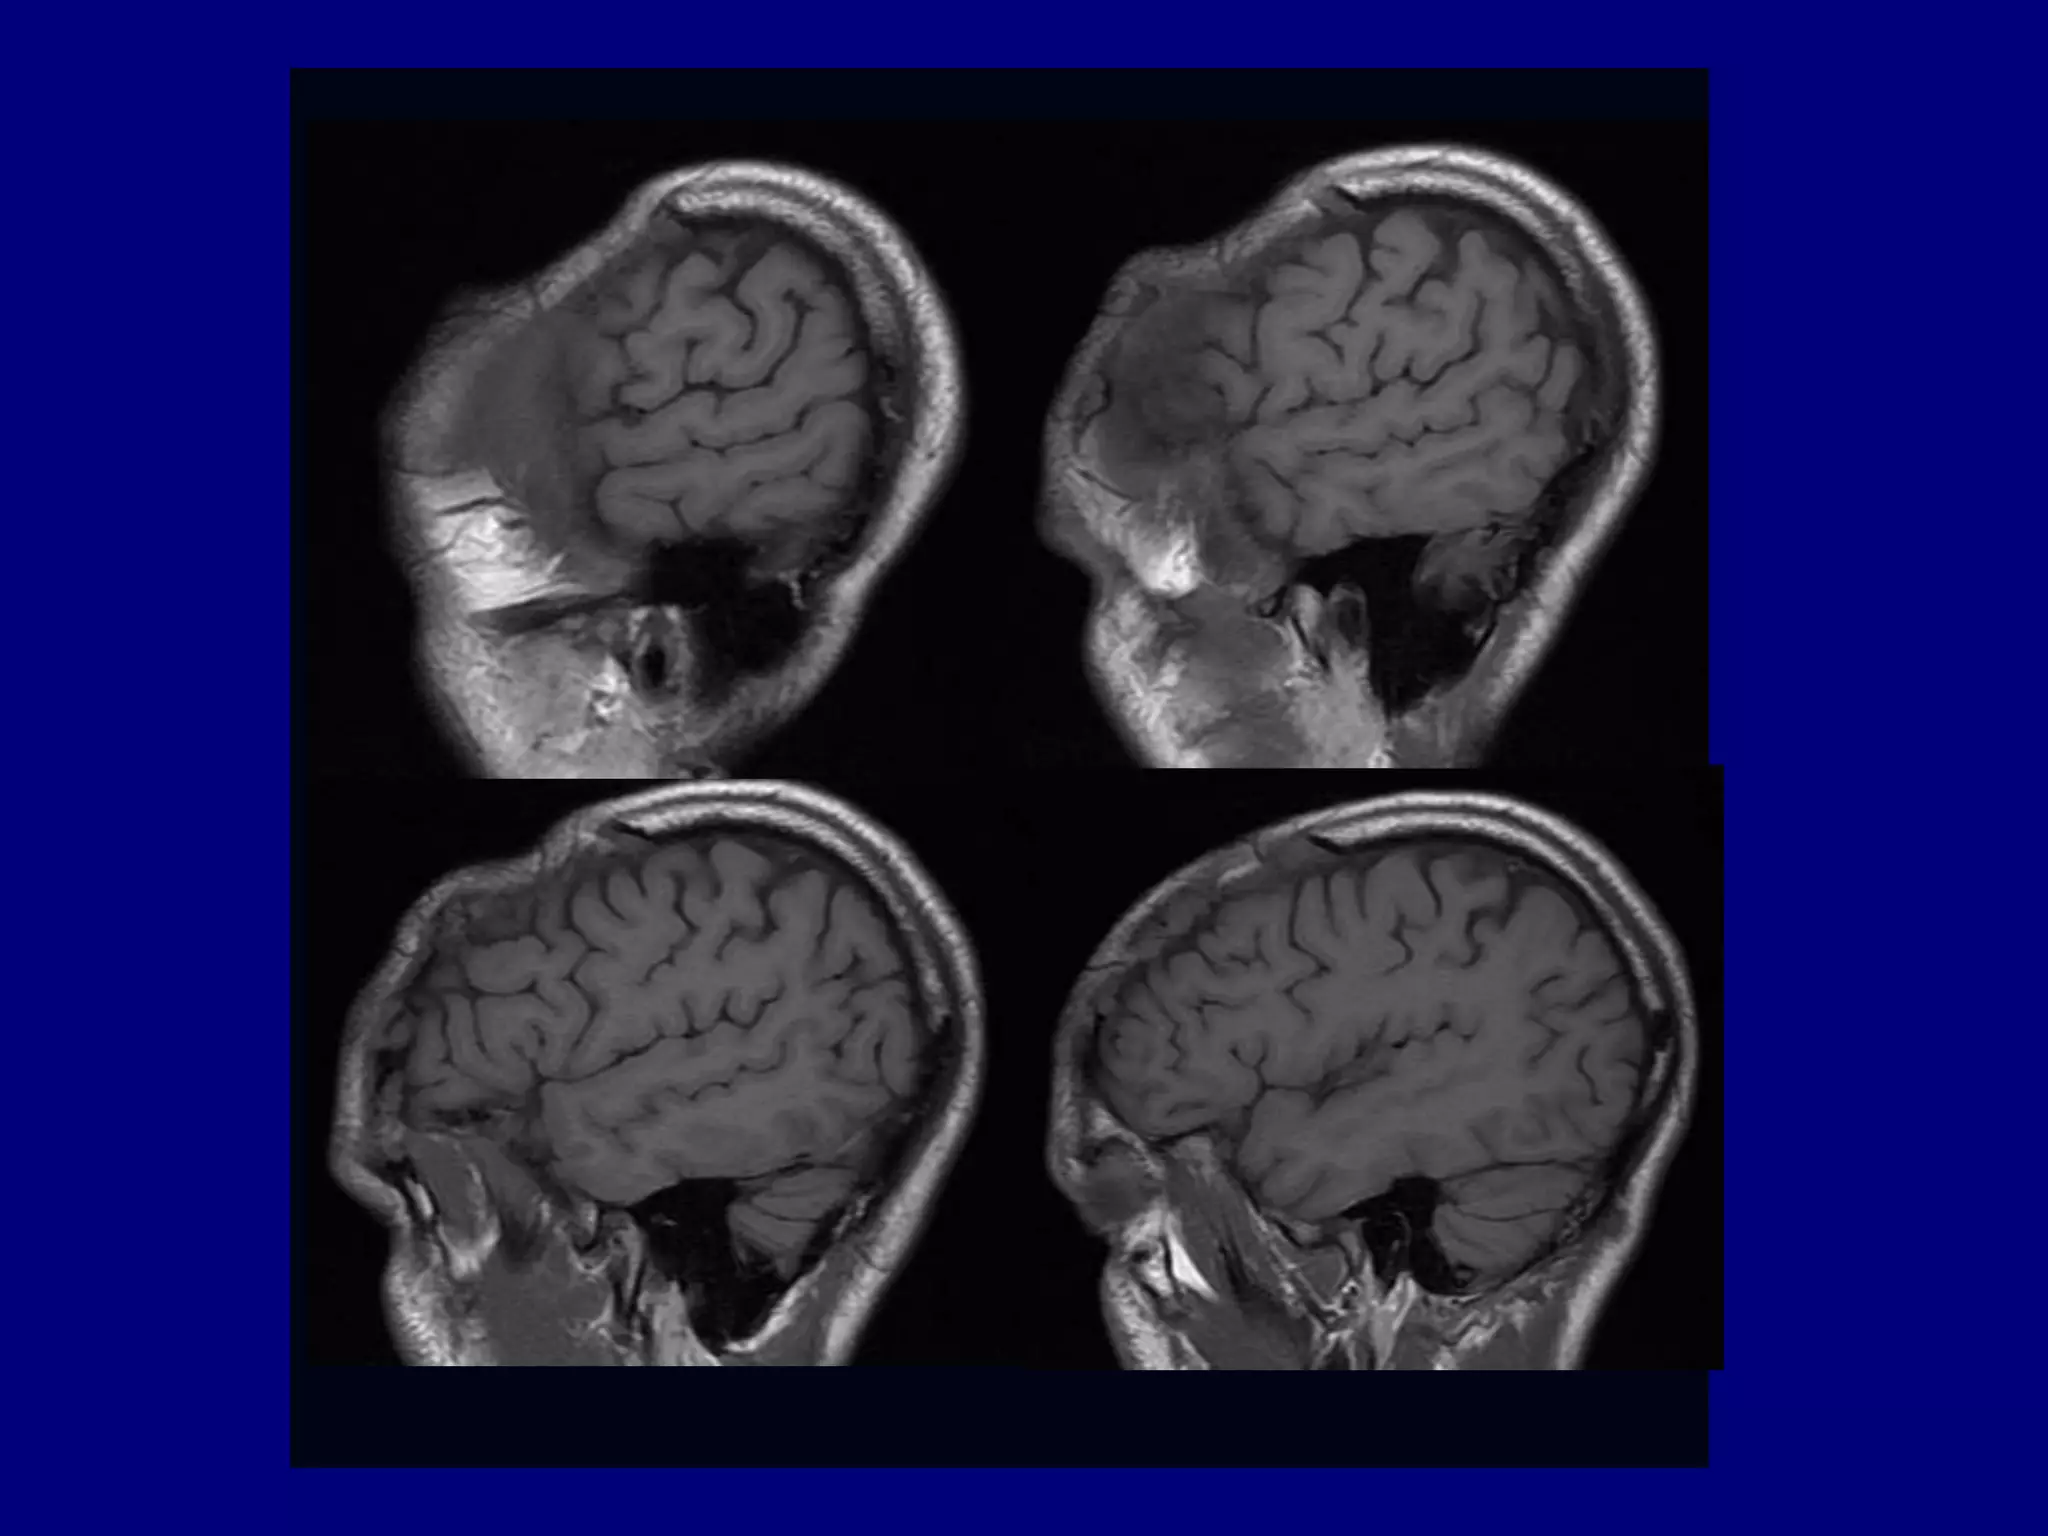

Magnetic Resonance Imaging

Post-gadolinium MPRAGE Sagittal and Coronal

Post-gadolinium MPRAGE Axial for Surgical Planning

MRI

Low signal central portion on T1 and T2-weighted

images indicating fibrosis

 Enhancement at the margins suggestive of

hemangiomatous active component of the disease

Lo et al AJNR 2004 25: 415-418